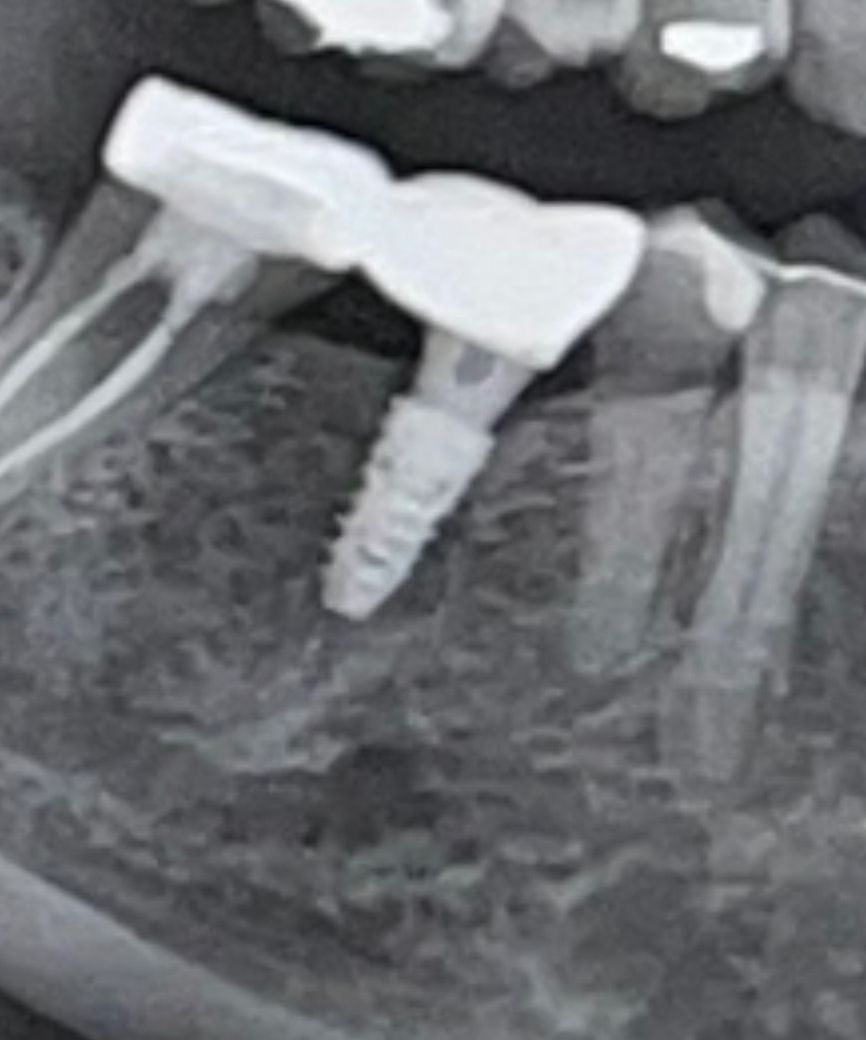

최근 치과에서 찍은 사진인데 혹시 임플란트에 염증이 있나요..? 피가 나거나 아프진 않은데 임플란트 옆 치아 잇몸이 살짝 부어있어서요.. 답변 꼭 부탁드립니다

사진상으로 봤을 경우에는 임플란트 뿌리 주변에 뼈가 손실된 것으로 보입니다. 임플란트의 별다른 느낌이나 불편감이 없다면 그대로 사용해도 될 것으로 생각됩니다. 하지만 임플란트에 너무 강하지 않게 힘을 작용해서 쓰는 것이 좋을 것으로 생각됩니다.

정확한건 치근단 사진을 찍어봐야 할 것 같은데 임플란트 주위 잇몸뼈가 약간씩 녹아있습니다 이는 염증으로 인한 것일 수 있습니다